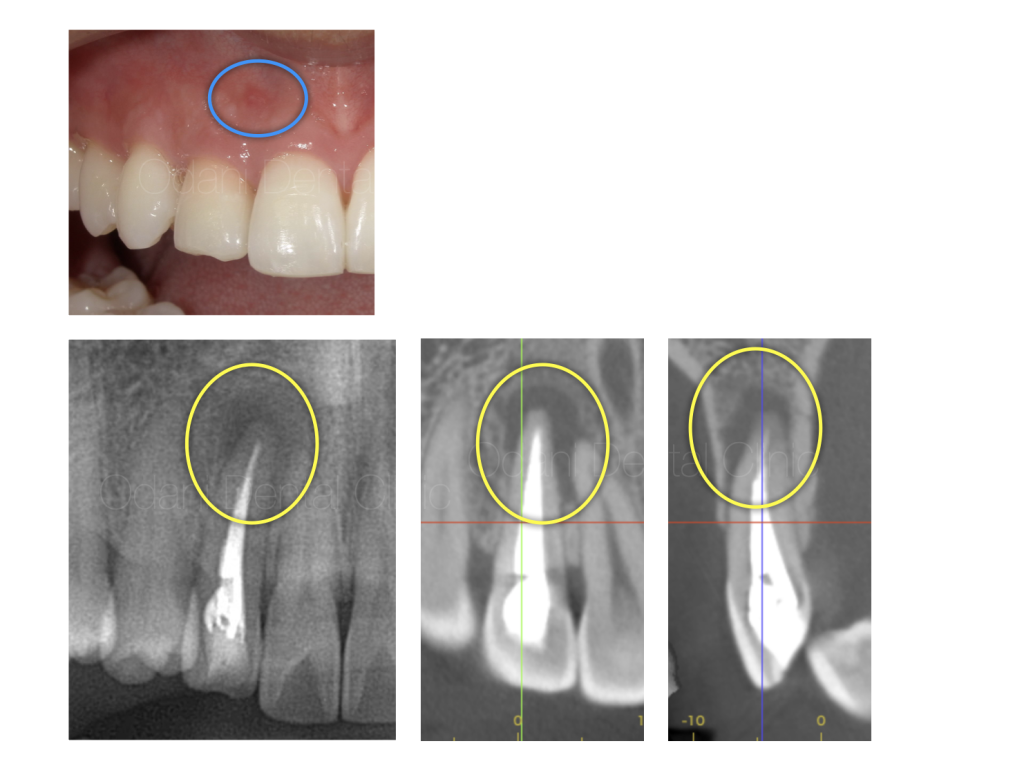

- 年齢・性別:20代男性

- 主訴:右上前歯の根の先の辺りに違和感がある

数年前に他院にて根管治療を行ったが、根の先の辺りに違和感があり、再根管治療を希望して当院に来院されました。

診察および画像検査の結果、根管内が感染しており、それに伴う炎症反応によって歯ぐきが腫れている(青丸)と考えられました。また、

CT画像では、歯の根の周囲の骨が広範囲に吸収していることが確認でき(黄色の丸)、該当歯だけでなく隣の歯が感染に巻き込まれている可能性があると考えられました。